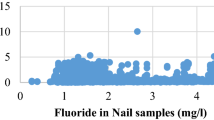

The fluoride level in surface waters is generally less than 1 mg/L. In deep groundwaters or in hot spring waters in contact with fluoride-rich minerals, this amount can be up to 20–53 mg/L (WHO 1994; Selinus 2005; Msonda et al. 2007; Yesilnacar et al. 2013, 2016; Yetis et al. 2019).

X-ray diffraction (XRD) and X-ray fluorescence (XRF) modalities were analyzed on a total of 108 samples in order to determine mineralogical compositions and chemical constituents, with 62 samples from Karataş village and 46 from Sarım. The mineral composition according to depth is illustrated in Fig. 2. The chemical substances obtained from the XRF analysis were SiO2, Al2O3, Fe2O3, MgO, CaO, K2O, TiO2, P2O5, and LOI (loss on ignition). Similarly, Calcite, Quartz, Cu, Ni, S, Sr, Zn, and Zr substances were determined from the XRD analysis. It should be noted that in the XRD analysis, Cu, Ni, S, Sr, Zn, and Zr parameters are represented in ppm scale and the remaining are in percentage form. Some basic statistical information of these compounds and substances for the XRD and XRF modalities are listed in Table 1.

XRD and XRF features were utilized as the input parameters of the proposed models, as shown in Table 2. Field experts specified two distinct fluorosis levels based on fluoride content in the drinking water obtained from the Karataş and Sarım wells. Those levels constituted the class labels, or output, of the proposed models. The models were evaluated by the Naïve Bayes as a linear, and ANN and SVM as non-linear classifiers with 10-fold cross-validation technique. Weka machine learning software written in Java was used for the learning algorithms (Hall et al. 2009). Classification performances of the proposed models are shown in Table 3.

where FDP is Fisher discrimination power, and μ and σ depict the mean and variance of each class, respectively. Figures 4 and 6 highlight the influence of each variable based on between-class scatter/distribution as a box-plot visualization and Fisher scores. In order to unify distribution ranges of parameters, z-score normalization was applied. It should be noted that in Fig. 6, the notches represent medians and edges of the boxes lie between the 25th and 75th percentiles. In addition, “+” pointers are used to indicate the outliers in the distribution. Class separation quality is determined by the distance between notches and its level of overlap. The highest gap between notches and the smallest overlap represents good class separation power of the feature. In Fig. 4, the features having relatively higher discrimination powers have higher FDP scores, and from this perspective, both Figs. 4 and 6 are in agreement. It can therefore be inferred from these figures that the XRF variables have higher discrimination power potential than the XRD attributes, and that the most salient feature is Zr and CaO from XRD and XRF, respectively.